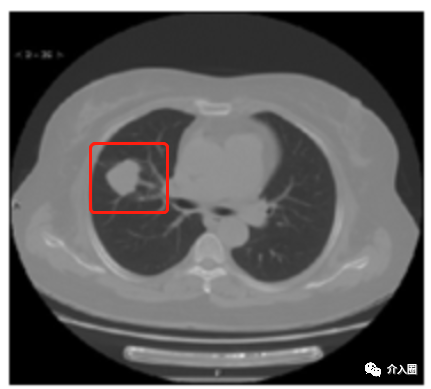

患者信息:女性,64歲,病灶位于右肺上葉前段,呈分葉狀,牽拉臨近胸膜,病灶大小為3.4x3.0x2.7cm,臨床診斷為肺腺癌

治療方案及過程:給予CT引導下冷凍消融治療術

治療結果:術后6個月復查病灶完全壞死

▲圖2 術前